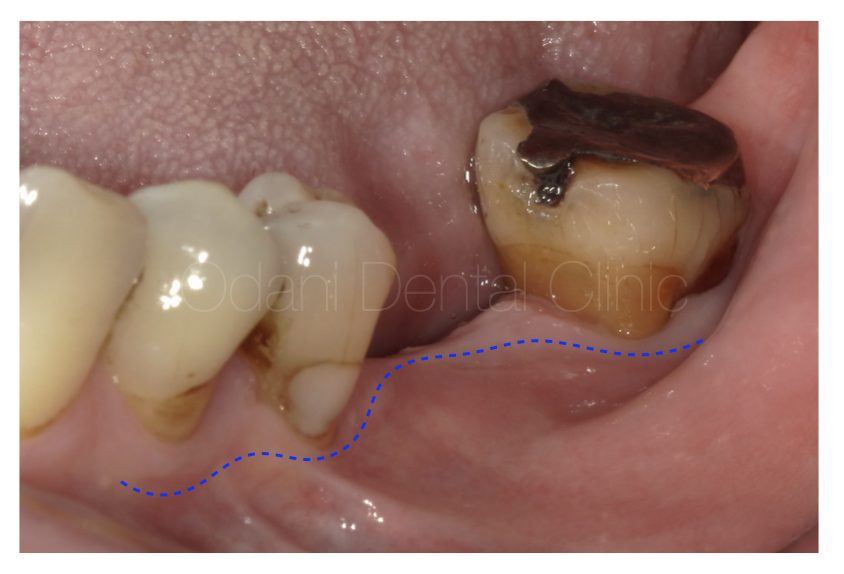

このように歯ぐきが大きく不足している場合(青色の点線)、そのままの歯ぐきの状態で進んでしまうと「磨けない」=「長持ちにつながらない」結果が予測されますので、歯ぐきを歯肉移植により再生し、ゴシゴシ磨けて長期安定する環境づくりに努めます。

最終的に予後不良の一番奥の歯は抜歯し、結果としてインプラントがより清掃しやすい環境となりました。

歯と歯ぐきと骨の連続性が得られ、すべてが管理しやすい状態となりました。